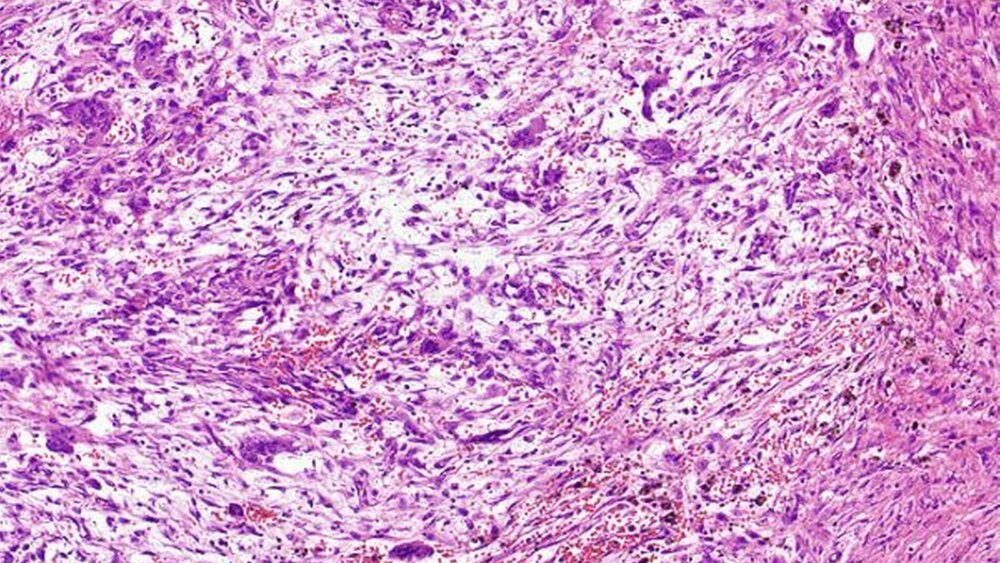

Die histopathologische Aufarbeitung des Gewebes ergab viele Riesenzellen vom osteoklastären Typ (Abbildung 4). Abschließend stellte sich die Diagnose eines Osteoklastoms, ein sogenanntes zentrales Riesenzellgranulom.